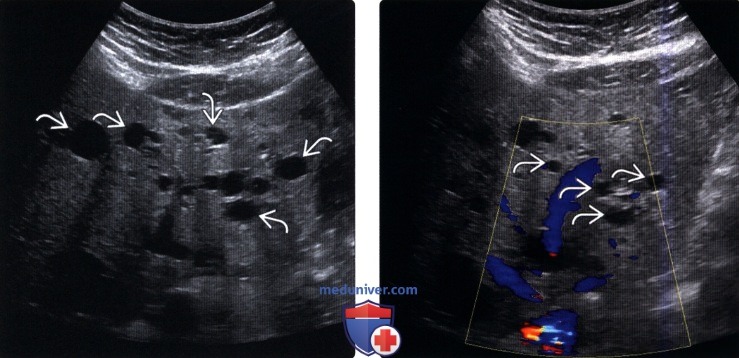

Лапароскопия — традиционный и достаточно эффективный метод в диагностике печеночных кист.

По мнению Б.И. Альперовича и соавт. (1985) и Н.А. Бражниковой (1988), метод особенно эффективен при кистах описторхозного генеза, расположенных, как правило, поверхностно. Это небольших размеров тонкостенные образования с прозрачным содержимым. Они чаще локализуются на диафрагмальной поверхности левой доли печени. Большой растянутый желчный пузырь и холангиоэктазы на вентральной поверхности печени подтверждают описторхозную природу найденных образований. Лапароскопия особенно информативна при локализации кист во II, III, V сегментах и нижней части IV сегмента. Хорошо просматриваются медиальная часть VI сегмента, но осмотр VII и VIII сегментов затруднителен.

Кисты печени необходимо дифференцировать с паразитарными кистами при эхинококкозе и описторхозе, большими полостями распада при альвеококкозе и раке печени. При паразитарных кистах характерна ультразвуковая и рентгенологическая картина (обызвествление капсулы, наличие дочерних пузырей, характерные изменения желчевыводящих протоков при описторхозной инвазии), а также иммунологические реакции.

При альвеококкозе с большими паразитарными кавернами стенки последних неровные и значительно толще, чем при обычных кистах, в полости могут быть секвестры. При раке быстрый рост опухоли и прогрессирующая кахексия, положительная реакция на α-фетопротеин.